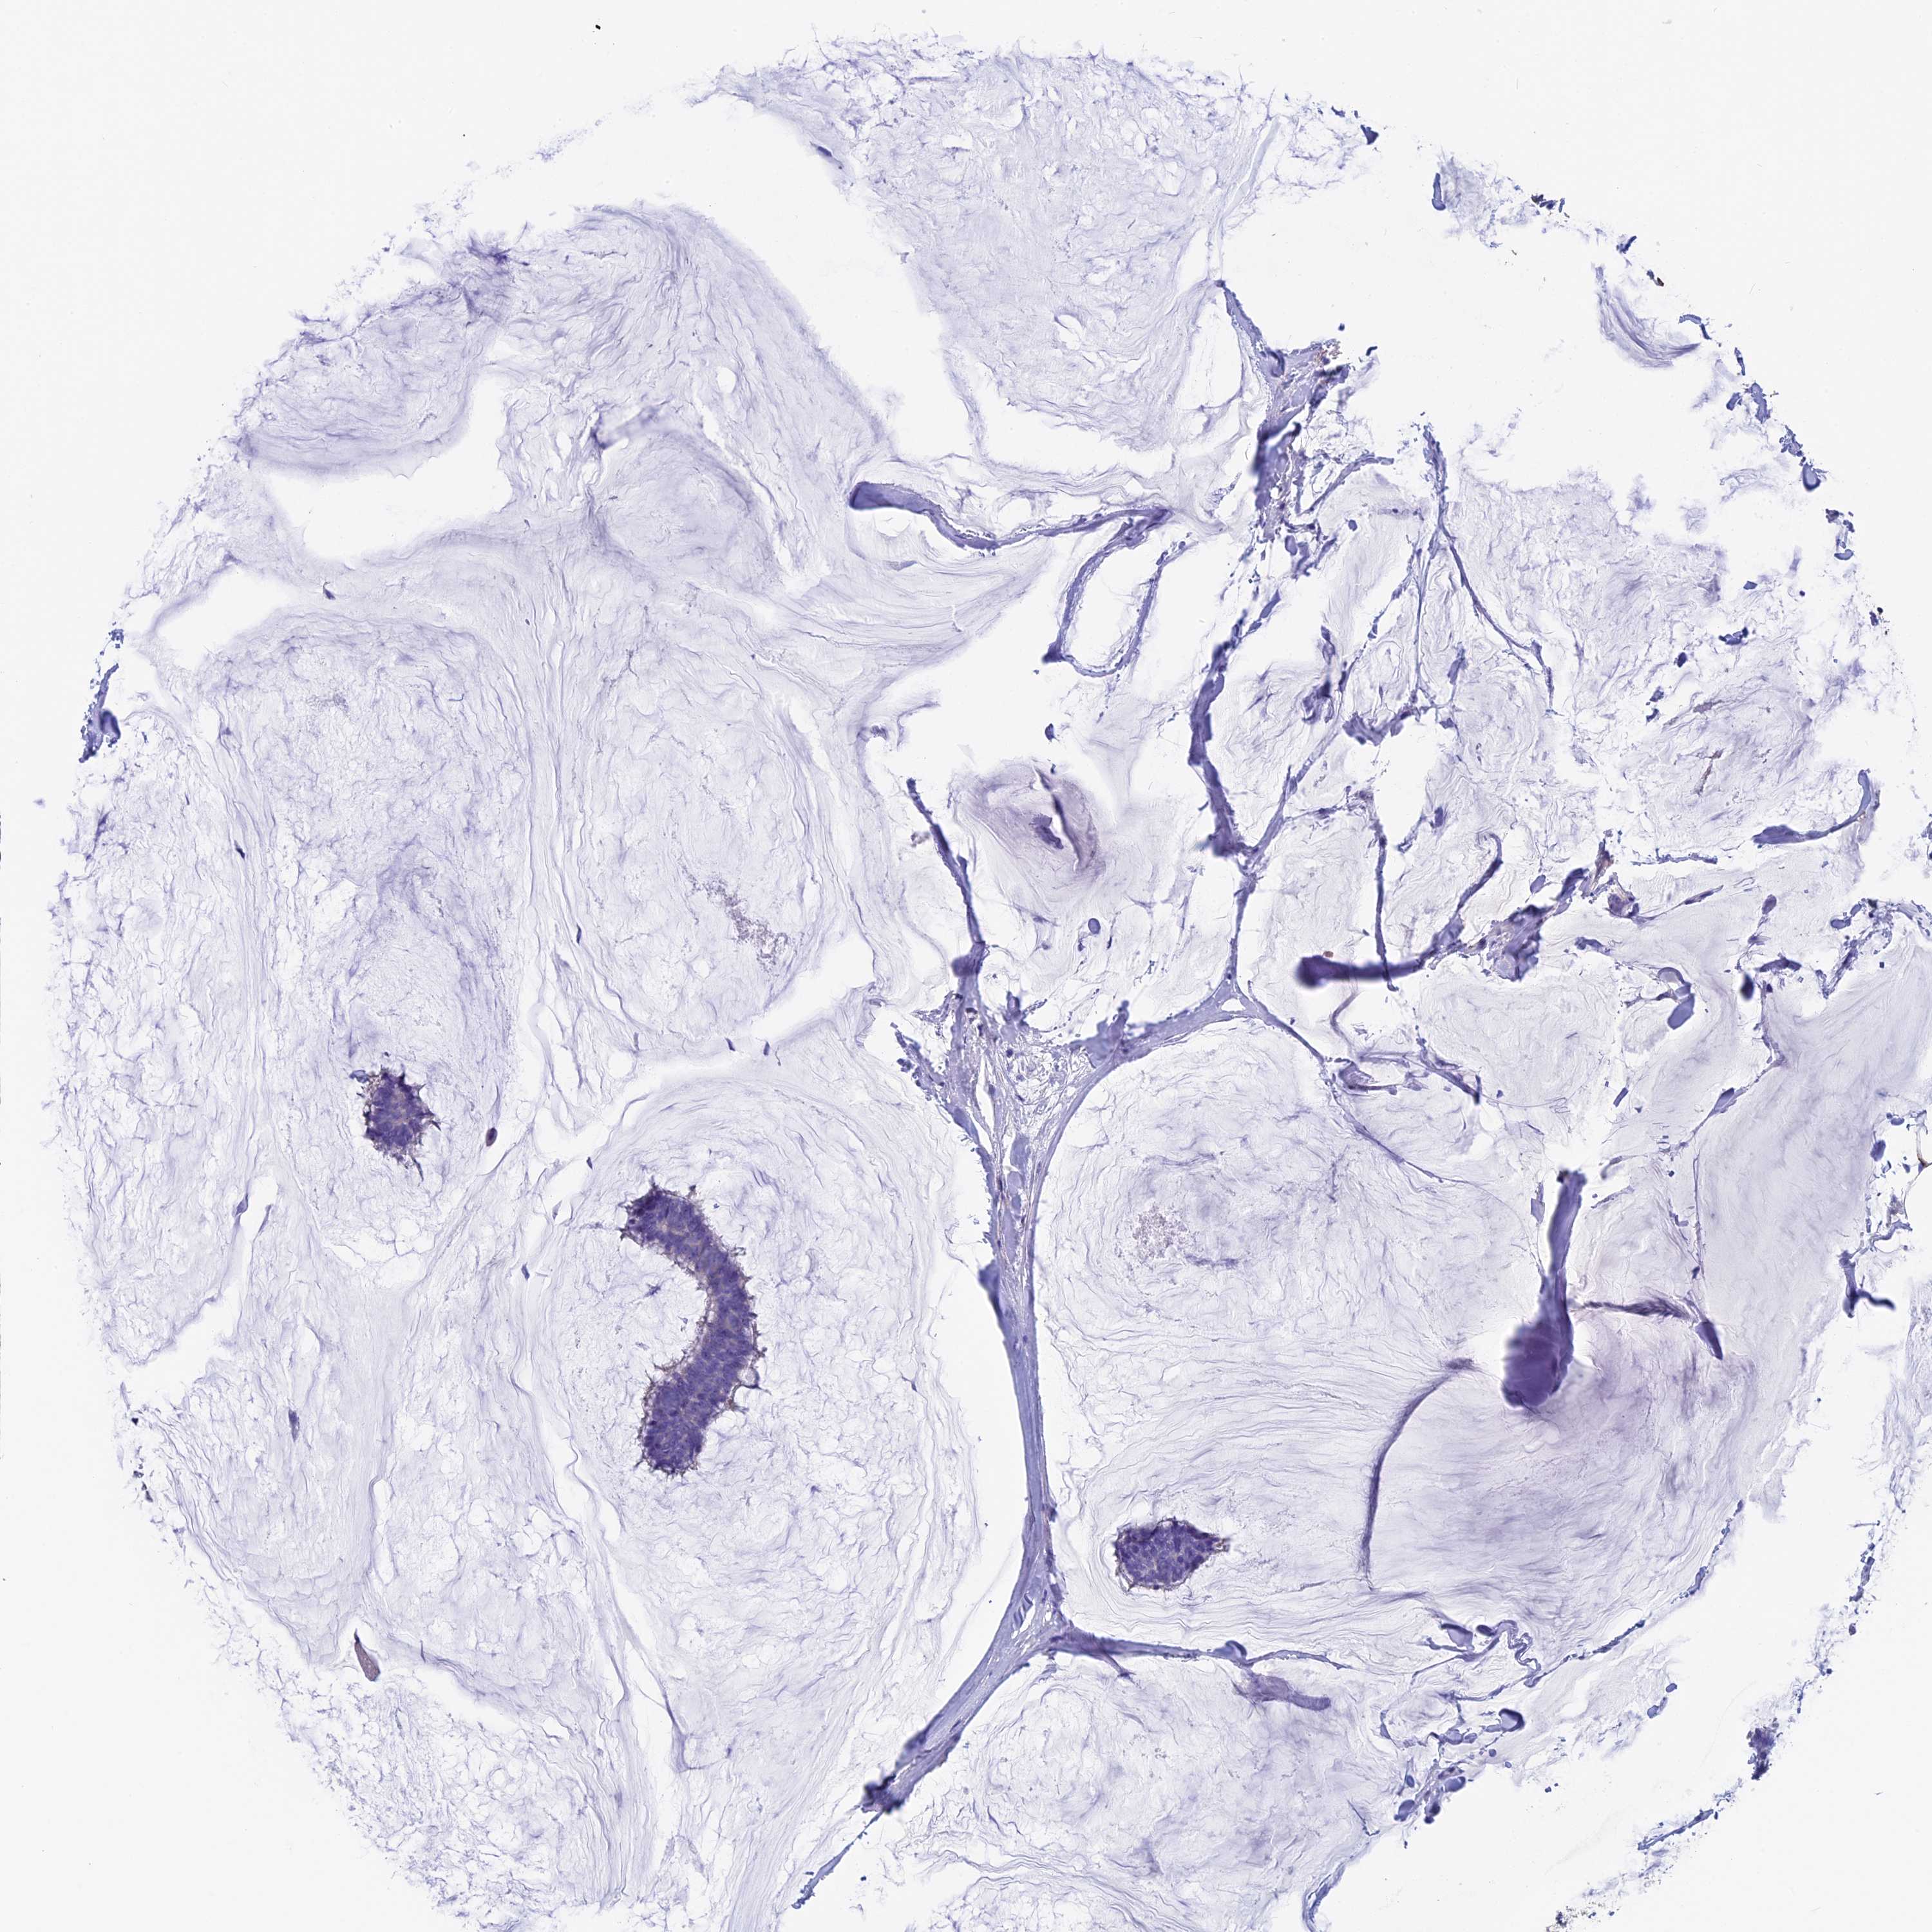

Breast cancer

Human cancer